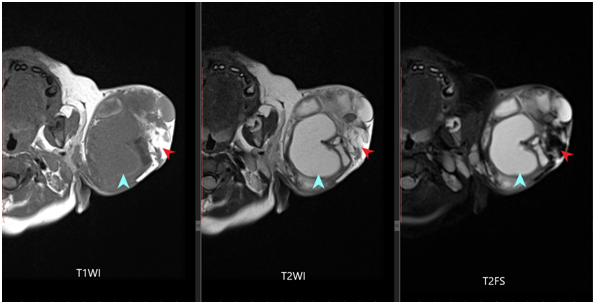

Figure 2 T1W, T2W and T2W FS images of the patient showing extracranial well defined lesion in the temporo-parietal region on left side with areas of cystic (blue arrowhead) and fat intensity (red arrowhead) within.